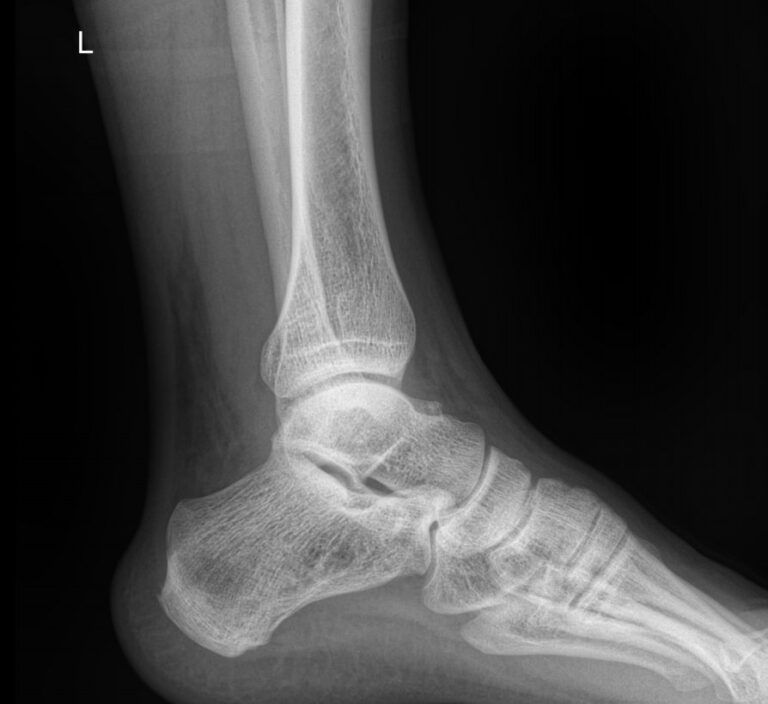

Сустав, соединяющий голень и стопу, наряду с коленным, выполняет важные функции перемещения тела в пространстве и поднятия собственного веса. Голеностоп имеет сложное строение и, как и любой другой сустав в теле человека, подвержен системным заболеваниям и травмам.

В диагностике патологий голеностопных суставов рентгеновское исследование относится к скрининговым, то есть первичным, методам. Действительно, рентген ― классический, простой, доступный и безболезненный способ получить информацию о внутреннем строении и патологических изменениях, произошедших в суставе. А благодаря современным цифровым аппаратам исследование становится и практически безопасным, так как несет минимальную дозу облучения.

Что покажет рентген голеностопного сустава

В описании врач указывает патологические изменения, если они есть в следующих образованиях:

• Суставные щели;

• Соответствие друг другу суставных поверхностей;

• Костная ткань и надкостница;

• Мягкие ткани.

Также подробно описываются переломы, вывихи, новообразования, их местоположение и особенности.